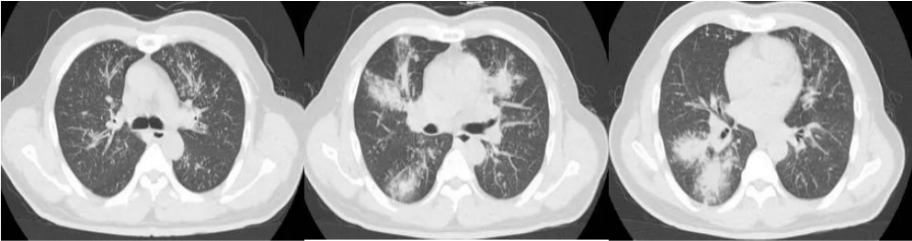

IAPA在发展过程中,较早可出现咳嗽、咳痰,进而出现呼吸困难、呼吸衰竭、缺氧性ARDS,进展迅速,即使气管插管、建立人工气道,患者也常出现气道峰压逐渐升高、潮气量逐渐下降,常因呼吸衰竭而无法挽救。但因其临床表现不特异,导致早期识别存在一定困难。(1)气管-支气管侵袭征象:沿支气管分布的结节及斑片影。对于没有基础疾病的重症流感病毒性肺炎患者,粒细胞数量正常,在曲霉感染后肺组织内会出现白细胞介导的强烈的炎症反应,导致渗出性支气管炎、支气管或肺泡受损及出血坏死,但直接侵袭血管的曲霉丝较少且主要以非增殖状态存在,因此多出现弥漫全肺的非特异性气道受侵型表现,而血管受侵型表现少见。如下图所示,第1天,支气管壁似乎有轻度增厚。病情进展至第4天,支气管壁明显增厚。随后迅速发展为支气管周围炎,并沿支气管侵袭、播散。图源:Respirol Case Rep, 2016, 4(1):32-34.注:双下肺实变,沿支气管血管束分布的实变、空洞,斑片状渗出影。注:支气管壁增厚、树芽征和沿着支气管血管束分布的实变。(2)对于免疫抑制宿主,可出现典型的曲霉感染影像学表现,例如实变与空洞伴晕征、空洞内有丝状结构及悬浮结节。注: A图见多叶肺炎和严重的小叶中心性、节旁性肺气肿; B图见右肺中叶空洞性浸润, 右肺下叶致密实变。图源:Chest, 2021, 160(2):e181-e184.注:A图可见实变、空洞,空洞内见丝状结构及悬浮结节;B图可见空洞、空气新月征。IAPA一种特殊的类型——侵袭性气管支气管炎,在支气管镜直视下可见气管和/或支气管溃疡、斑块或结节、假膜,是其典型表现。图源:国际呼吸杂志, 2023, 43(4):448-453.肺活检组织、气道斑块、假膜或溃疡的活检/刷检标本中发现真菌菌丝等特征性病理表现,可作为确诊标准。此外,在痰、支气管抽吸物、支气管肺泡灌洗液(BALF)中找到曲霉菌丝也可作为临床诊断标准。图源:Lancet Respir Med, 2018, 6(10):782-792.注:支气管活检组织病理显示有坏死物质和真菌成分,菌丝呈分枝状。图源:Chest, 2021, 160(2):e181-e184.图源:Tuberc Respir Dis (Seoul), 2014, 77(3):141-144.半乳甘露聚糖(galactomannan,GM)是曲霉特有的细胞壁多糖成分。菌丝生长时,半乳甘露聚糖是最早释放的抗原,是早期检测曲霉感染的经典方法。主要包括血清GM试验和BALF GM试验。血清GM试验在非粒细胞缺乏患者敏感性较低,仅为50%左右;ICU IPA患者的血清GM试验敏感性仅为30%~50%。在IAPA患者中,当以0.5作为GM试验阳性阈值时,诊断率仅20%。对于非中性粒细胞减少患者,BALF GM试验比血清GM试验具有更高的IPA诊断效率。EORTC/MSG标准采用1.0作为单份BALF阳性阈值的标准,当同时联合血浆/血清GM试验阳性时,BALF标本阈值可下调至0.8。我国学者研究发现,当截断值从0.5增加到0.717时,BALF GM试验可以显著降低假阳性率。无论是2016年美国传染病学会(IDSA)发表的《曲霉病诊断和管理实践指南》,还是2017年欧洲临床微生物学和感染病学会(ESCMID)/欧洲医学真菌学联盟(ECMM)/欧洲呼吸学会(ERS)联合发表的《曲霉病的诊断和管理指南》,都提及血清曲霉特异性IgG抗体在慢性肺曲霉病中有最高的检测阳性率。但2023年Clin Microbiol Infect杂志发表的一篇文章显示,IPA组的曲霉IgG抗体水平明显高于非IPA组。采样时间为发病后1~3个月内亚组显著高于采样时间为发病后<1个月亚组,影像学出现肺部空洞性病变亚组显著高于非肺部空洞性病变亚组。经过对比发现,曲霉IgG抗体的特异性和阳性预测值显著低于BALF GM。PCR的优势在于不仅能检测出曲霉的属和种,还可通过识别CYP51A基因突变来判断是否存在三唑类耐药可能。标本选择顺序:BALF>血浆>血清,但已进行了抗真菌治疗患者的血样本PCR阳性预测值可从62%降至5%。单份PCR阴性结果可极大程度地排除IPA可能。PCR可能更适合用于可疑IAPA患者在拟行抗真菌治疗前的筛查以及治疗过程中的实时监测。mNGS优势在于覆盖能力广, 时效性好, 不受先前使用抗菌药物的影响, 并可提供病原鉴定分型、耐药基因及毒力因子分析。但其检测成本较高, 结果需要临床医生进行解读和判断, 标本选择以BALF为最佳。

患者男性,51岁,因“咳嗽、咳痰5天,发热伴呼吸困难3天”入院。入院前曾应用静脉激素。既往有胰腺癌病史,入院后发现血糖明显升高,并确诊2型糖尿病。乙型流感病毒核酸阳性。血清GM试验阴性,BALF GM >5 S/CO,曲霉IgG阴性,BALF mNGS提示烟曲霉(序列数809975),乙型流感病毒(序列数2732),BALF培养结果为烟曲霉,对伏立康唑耐药。患者胸部CT及气管镜结果如下图所示。患者,男性,36岁,因“咳嗽、咳痰1周,呼吸困难2天”入院。入院前2天外院诊断糖尿病酮症酸中毒、乙型流感病毒性肺炎,并有使用静脉激素。入院查乙型流感病毒核酸阳性。BALF GM>5 S/CO,血清GM 4.8 S/CO,曲霉IgG阴性,BALF mNGS提示烟曲霉(序列数25173),乙型流感病毒(序列数90),气道假膜钳夹组织及BALF培养烟曲霉。患者胸部CT及气管镜结果如下图所示。IAPA的发病率较高,且在不同的流感亚型中无显著差异。而且IAPA的病死率高,但早期临床表现缺乏特异性,诊断存在一定困难,应引起临床医师的高度关注。早期、准确地识别与诊断IAPA,及时启动抗真菌治疗是改善预后的关键。[1] Iuliano AD, Roguski KM, Chang HH, et al. Estimates of global seasonal influenza‑associated respiratory mortality: a modelling study[J]. Lancet, 2018, 391(10127):1285-1300. [2] Verweij PE, Rijnders BJA, Brüggemann RJM, et al. Review of influenza‑associated pulmonary aspergillosis in ICU patients and proposal for a case definition: an expert opinion[J]. Intensive Care Med, 2020, 46(8): 1524-1535.[3] Martin-Loeches I, J Schultz M, Vincent JL, et al. Increased incidence of co-infection in critically ill patients with influenza[J]. Intensive Care Med, 2017, 43(1):48-58.[4] ABBOTT JD, FERNANDO HV, GURLING K, et al. Pulmonary aspergillosis following post‑influenzal bronchopneumonia treated with antibiotics[J]. Br Med J, 1952, 1(4757):523-525. [5] Martin-Loeches I, J Schultz M, Vincent JL, et al. Increased incidence of coinfection in critically ill patients with influenza[J]. Intensive Care Med, 2017, 43:48-58.[6] Schauwvlieghe AFAD, Rijnders BJA, Philips N, et al. Invasive aspergillosis in patients admitted to the intensive care unit with severe influenza: a retrospective cohort study[J]. Lancet Respir Med, 2018, 6(10): 782-792.[7] Beumer MC, Koch RM, van Beuningen D, et al. Influenza virus and factors that are associated with ICU admission, pulmonary co-infections and ICU mortality[J]. J Crit Care, 2019, 50:59-65. [8] Huang L, Zhang N, Huang X, et al. Invasive pulmonary aspergillosis in patients with influenza infection: a retrospective study and review of the literature[J]. Clin Respir J, 2019, 13(4):202-211. [9] Krifors A, Blennow O, Påhlman LI, et al. Influenza-associated invasive aspergillosis in patients admitted to the intensive care unit in Sweden: a prospective multicentre cohort study[J]. Infect Dis (Lond), 2024, 56(2):110-115.[10] Lu LY, Lee HM, Burke A, et al. Prevalence, Risk Factors, Clinical Features, and Outcome of Influenza-Associated Pulmonary Aspergillosis in Critically Ill Patients: A Systematic Review and Meta-Analysis[J]. Chest, 2024, 165(3):540-558. [11] Delaney JW, Pinto R, Long J, Lamontagne F, et al. The influence of corticosteroid treatment on the outcome of influenza A (H1N1pdm09)‑related critical illness[J]. Crit Care, 2016, 20:75.[12] [Nedel WL, Nora DG, Salluh JI, et al. Corticosteroids for severe influenza pneumonia: A critical appraisal[J]. World J Crit Care Med, 2016, 5(1):89-95.[13] Wauters J, Baar I, Meersseman P, et al. Invasivepulmonary aspergillosis is a frequent complication of critically ill H1N1 patients: a retrospective study[J]. Intensive Care Med, 2012, 38(11):1761-1768.[14] Rodriguez-Goncer I, Thomas S, Foden P, et al. Invasive pulmonary aspergillosis is associated with adverse clinical outcomes in critically ill patients receiving veno‑venous extracorporeal membrane oxygenation[J]. Eur J Clin Microbiol Infect Dis, 2018, 37(7):1251-1257. [15] Cavayas YA, Yusuff H, Porter R. Fungal infections in adult patients on extracorporeal life support[J]. Crit Care, 2018, 22(1):98. [16] Clancy CJ, Nguyen MH. Acute community-acquired pneumonia due to Aspergillus in presumably immunocompetent hosts: clues for recognition of a rare but fatal disease[J]. Chest, 1998, 114:629-634.[17] Hasejima N, Yamato K, Takezawa S, et al. Invasive pulmonary aspergillosis associated with influenza B[J]. Respirology, 2005;10:116-119.[18] van de Sandt CE, Bodewes R, Rimmelzwaan GF, et al, Rimmelzwaan GF, de Vries RD. Influenza B viruses: not to be discounted[J]. Future Microbiol, 2015, 10(9):1447-1465. [19] Matias G, Taylor R, Haguinet F, et al. Estimates of mortality attributable to influenza and RSV in the United States during 1997-2009 by influenza type or subtype, age, cause of death, and risk status[J]. Influenza Other Respir Viruses, 2014, 8(5):507-515.[20] Kuek LE, Lee RJ. First contact: the role of respiratory cilia in host-pathogen interactions in the airways[J]. Am J Physiol Lung Cell Mol Physiol, 2020, 319(4):L603-L619.[21] Ghoneim HE, Thomas PG, McCullers JA. Depletion of alveolar macrophages during influenza infection facilitates bacterial superinfections[J]. J Immunol, 2013, 191(3):1250-1259.[22] Fox A, Le NM, Horby P, et al. Severe pandemic H1N1 2009 infection is associated with transient NK and T deficiency and aberrant CD8 responses[J]. PLoS One, 2012, 7(2):e31535.[23] Short KR, et al. Pathogenesis of influenza induced acute respiratory distress syndrome. Lancet Infect Dis. 2014;14(1): 57-69.[24] Dewi IM, et al. Neuraminidase and SIGLEC15 modulate the host defense against pulmonary aspergillosis. Cell Rep Med. 2021;2(5): 100289.[25] Ohta H, Yamazaki S, Miura Y, et al. Invasive tracheobronchial aspergillosis progressing from bronchial to diffuse lung parenchymal lesions[J]. Respirol Case Rep, 2016, 4(1):32-34.[26] Saha BK, Chong W. A 61-Year-Old Man With Influenza Pneumonia and New Onset Hemoptysis[J]. Chest, 2021, 160(2):e181-e184.[27] 罗丹心, 谷林, 阎锡新. 体外膜肺氧合治疗重症流感相关肺曲霉病1例并文献复习[J]. 国际呼吸杂志, 2023, 43(4):448-453.[28] Park DW, Yhi JY, Koo G, et al. Fatal clinical course of probable invasive pulmonary aspergillosis with influenza B infection in an immunocompetent patient[J]. Tuberc Respir Dis (Seoul), 2014, 77(3):141-144.[29] Meersseman W, Vandecasteele SJ, Wilmer A, et al. Invasive aspergillosis in critically ill patients without malignancy[J]. Am J Respir Crit Care Med, 2004, 170(6):621-625.[30] Lahmer T, Neuenhahn M, Held J, et al. Comparison of 1,3-β-dglucan with galactomannan in serum and bronchoalveolar fluid for the detection of Aspergillus species in immunosuppressed mechanical ventilated critically ill patients[J]. J Crit Care, 2016, 36:259-264.[31] Zhu N, Zhou D, Xiong W, et al. Performance of mNGS in bronchoalveolar lavage fluid for the diagnosis of invasive pulmonary aspergillosis in non-neutropenic patients[J]. Front Cell Infect Microbiol, 2023, 13:1271853.[32] Patterson TF, Thompson GR 3rd, Denning DW, et al. Practice Guidelines for the Diagnosis and Management of Aspergillosis: 2016 Update by the Infectious Diseases Society of America[J]. Clin Infect Dis, 2016, 63(4):e1-e60. [33] Ullmann AJ, Aguado JM, Arikan-Akdagli S, et al. Diagnosis and management of Aspergillus diseases: executive summary of the 2017 ESCMID-ECMM-ERS guideline[J]. Clin Microbiol Infect, 2018, 24 Suppl 1:e1-e38. [34] Lu Y, Liu L, Li H, et al. The clinical value of Aspergillus-specific IgG antibody test in the diagnosis of nonneutropenic invasive pulmonary aspergillosis[J]. Clin Microbiol Infect, 2023, 29(6):797.e1-797.e7. [35] Donnelly JP, Chen SC, Kauffman CA, et al. Revision and Update of the Consensus Definitions of Invasive Fungal Disease From the European Organization for Research and Treatment of Cancer and the Mycoses Study Group Education and Research Consortium[J]. Clin Infect Dis, 2020, 71(6):1367-1376.[36] Springer J, White PL, Hamilton S, et al. Comparison of performance characteristics of Aspergillus PCR in testing a range of blood-based samples in accordance with international methodological recommendations[J]. J Clin Microbiol, 2016, 54(3):705-711.[37] Eigl S, Hoenigl M, Spiess B, et al. Galactomannan testing and Aspergillus PCR in same-day bronchoalveolar lavage and blood samples for diagnosis of invasive aspergillosis[J]. Med Mycol, 2017, 55(5):528-534.[38] Mengoli C, Cruciani M, Barnes RA, et al. Use of PCR for diagnosis of invasive aspergillosis: systematic review and meta-analysis[J]. Lancet Infect Dis, 2009, 9(2):89-96.[39] Springer J, Lackner M, Nachbaur D, et al. Prospective multicentre PCR-based Aspergillus DNA screening in high-risk patients with and without primary antifungal mould prophylaxis[J]. Clin Microbiol Infect, 2016, 22(1):80-86.[40] 施毅, 赵江南. 侵袭性真菌病病原学非培养实验室诊断方法[J]. 中华结核和呼吸杂志, 2019, 42(7):500-505[41] Eigl S, Prattes J, Lackner M, et al. Multicenter evaluation of a lateral-flow device test for diagnosing invasive pulmonary aspergillosis in ICU patients[J]. Crit Care, 2015, 19(1):178.[42] Jenks JD, Mehta SR, Taplitz R, et al. Point-of-care diagnosis of invasive aspergillosis in non-neutropenic patients: aspergillus galactomannan lateral flow assay versus aspergillus-specific lateral flow device test in bronchoalveolar lavage[J]. Mycoses, 2019, 62(3):230-236.[43] Maertens JA, Raad II, Marr KA, et al. Isavuconazole versus voriconazole for primary treatment of invasive mould disease caused by Aspergillus and other filamentous fungi (SECURE): a phase 3, randomised-controlled, non-inferiority trial[J]. Lancet, 2016, 387(10020):760-769.[44] Maertens JA, Rahav G, Lee DG, et al. Posaconazole versus voriconazole for primary treatment of invasive aspergillosis: a phase 3, randomised, controlled, non-inferiority trial[J]. The Lancet, 2021, 397(10273):499-509.[45] Thompson 3rd GR, Soriano A, Cornely OA, et al. Rezafungin versus caspofungin for treatment of candidaemia and invasive candidiasis (ReSTORE): a multicentre, double-blind, double-dummy, randomised phase 3 trial[J]. Lancet, 2023, 401(10370):49-59.[46] Shaw KJ, Ibrahim AS. Fosmanogepix: A Review of the First-in-Class Broad Spectrum Agent for the Treatment of Invasive Fungal Infections[j]. J Fungi (Basel), 2020, 6(4):239. [47] Petraitis V, Petraitiene R, Katragkou A, et al. Combination Therapy with Ibrexafungerp (Formerly SCY-078), a First-in-Class Triterpenoid Inhibitor of (1→3)-β-d-Glucan Synthesis, and Isavuconazole for Treatment of Experimental Invasive Pulmonary Aspergillosis[J]. Antimicrob Agents Chemother, 2020, 64(6):e02429-19.[48] Wiederhold NP. Review of the Novel Investigational Antifungal Olorofim[J]. J Fungi (Basel), 2020, 6(3):122. [49] Zhou M, Liu L, Cong Z, et al. A dual-targeting antifungal is effective against multidrug-resistant human fungal pathogens[J]. Nat Microbiol, 2024, 9(5):1325-1339.